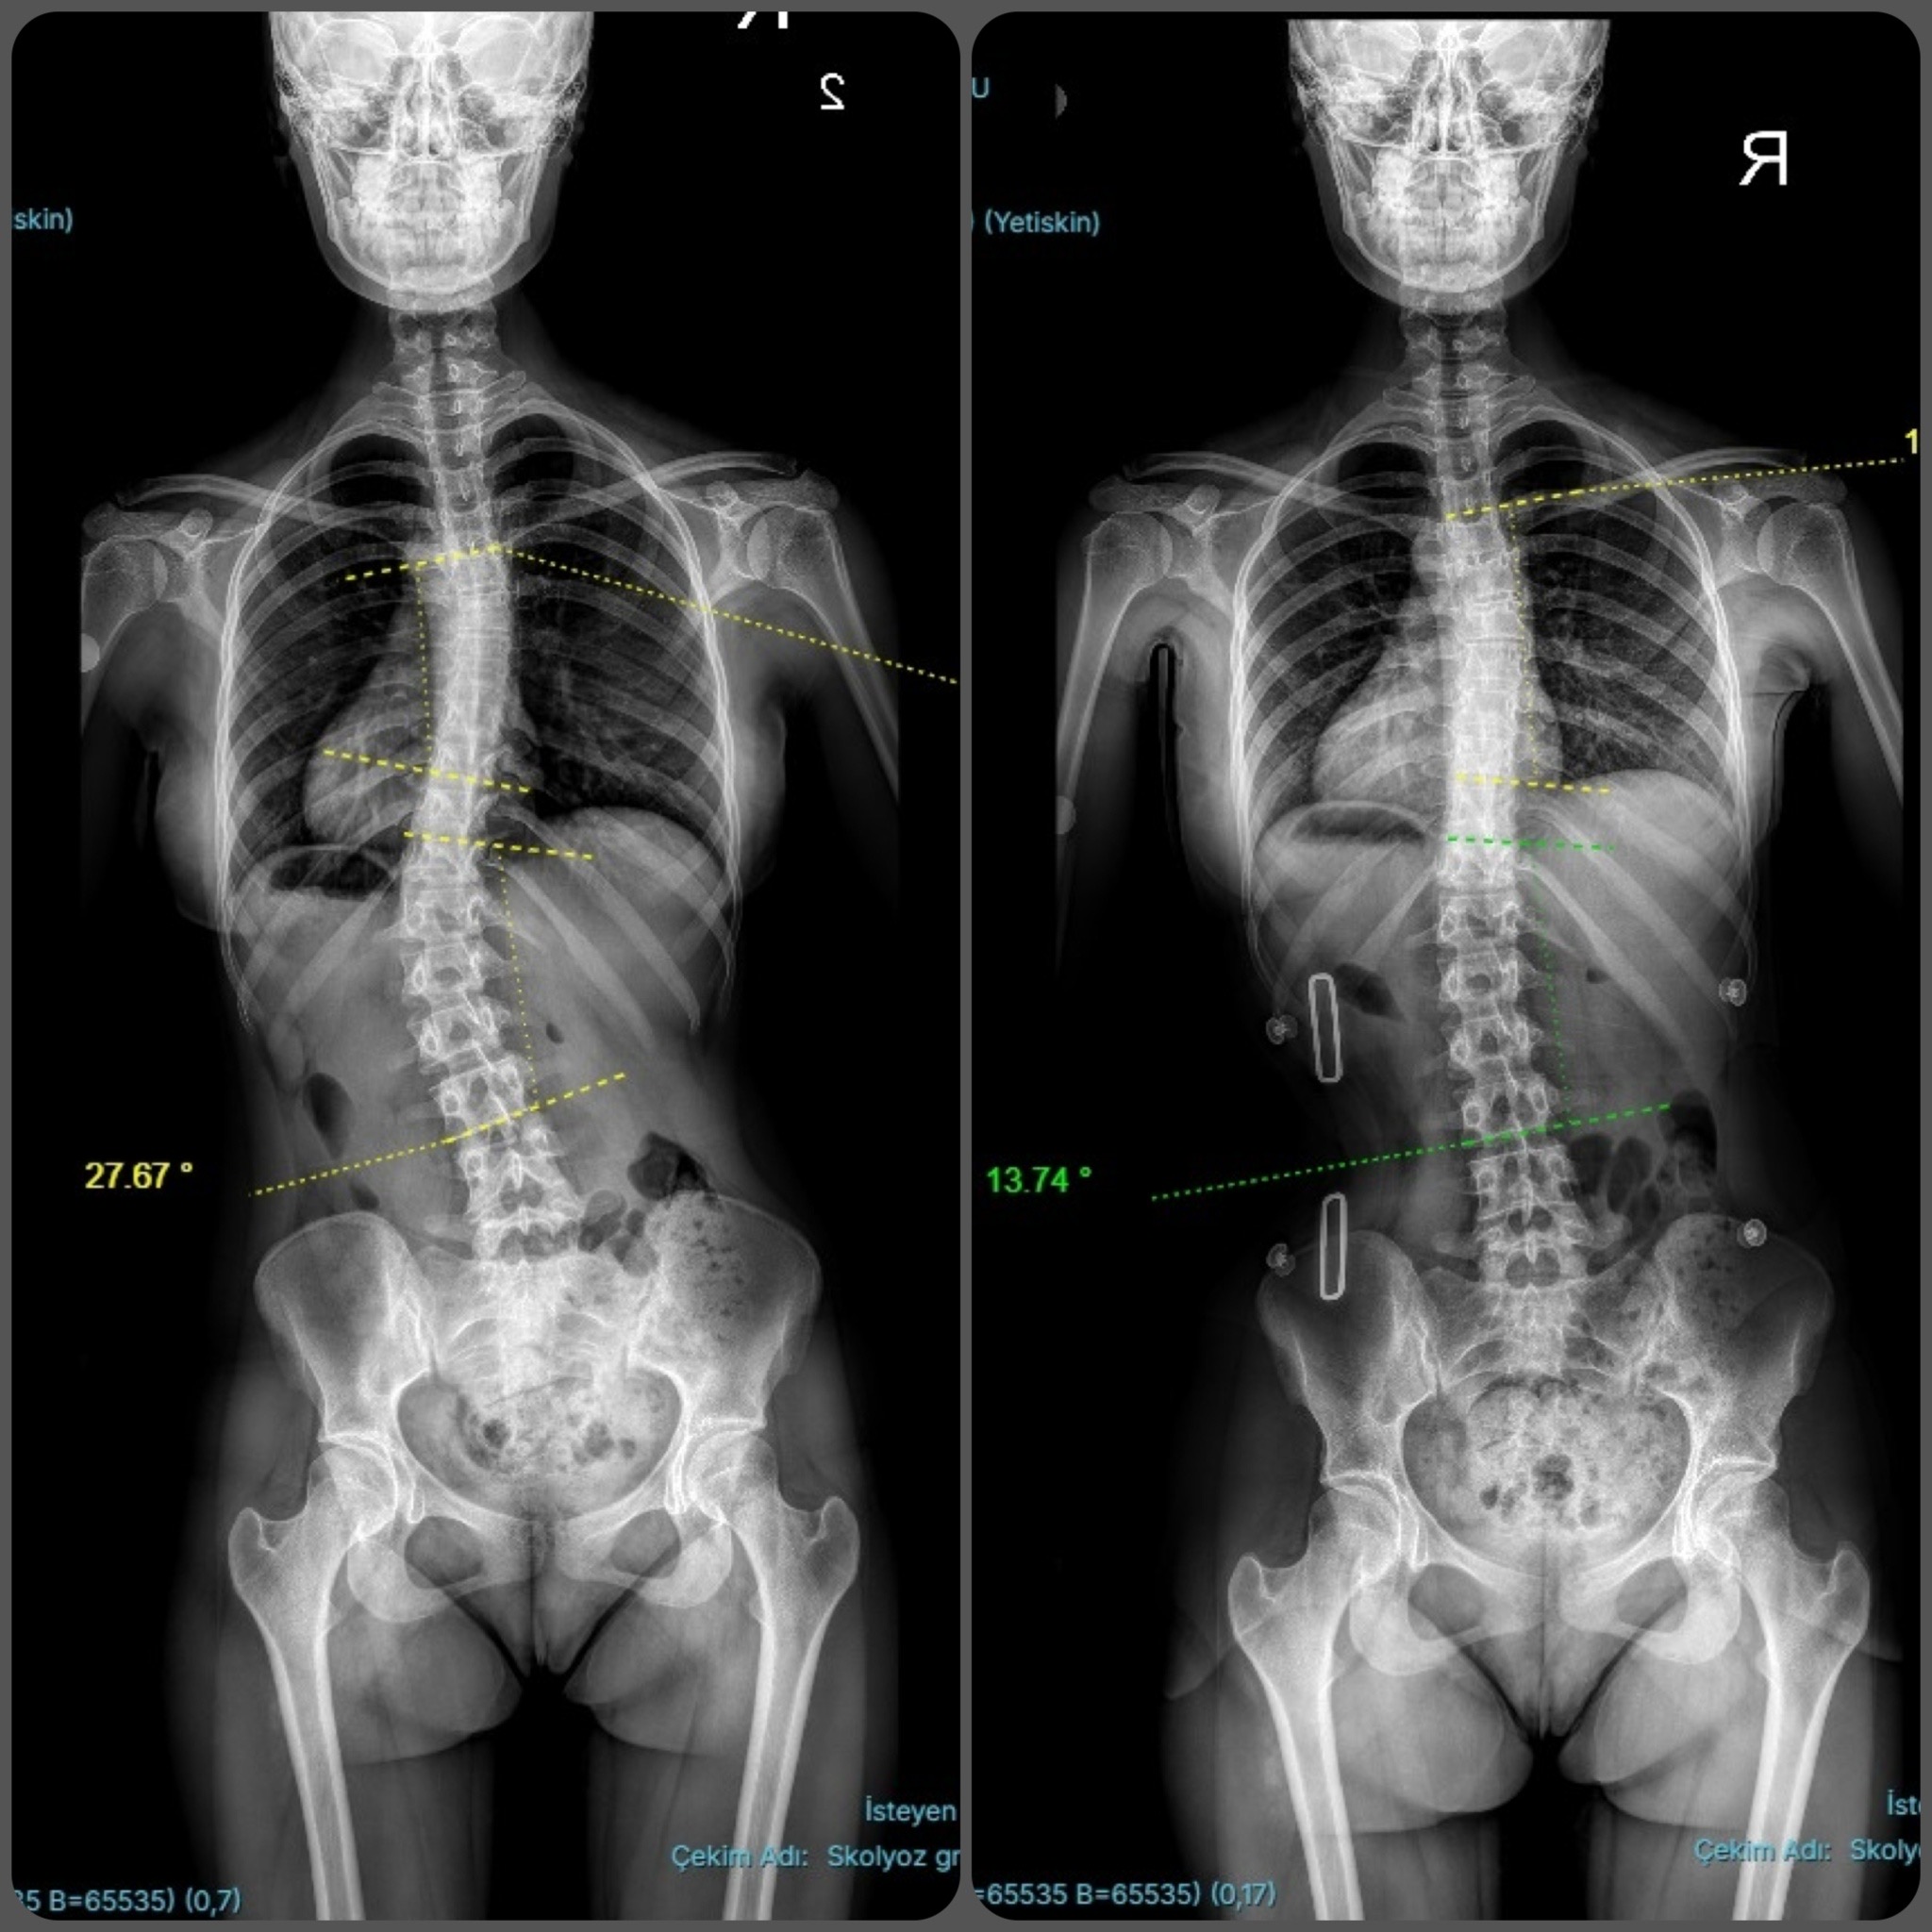

CAD/CAM (Bilgisayar Destekli Tasarım) sistemlerimizle, röntgen üzerindeki eğrilik derecesine (Cobb açısı) tam zıt kuvvet uygulayan, asimetrik Gensingen/Cheneau tipi korseler tasarlıyoruz.

Uyguladığımız 3D korseler ile elde ettiğimiz düzeltme sonuçlarından bazı örnekler.